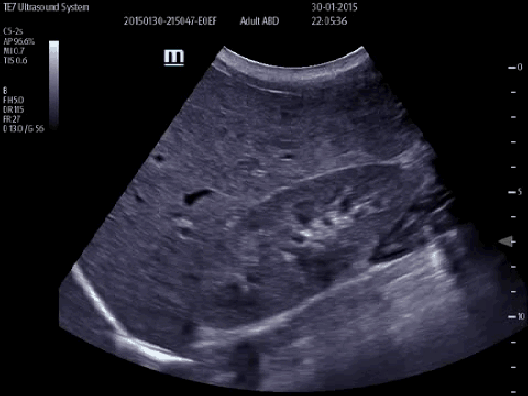

Obrazowanie kliniczne